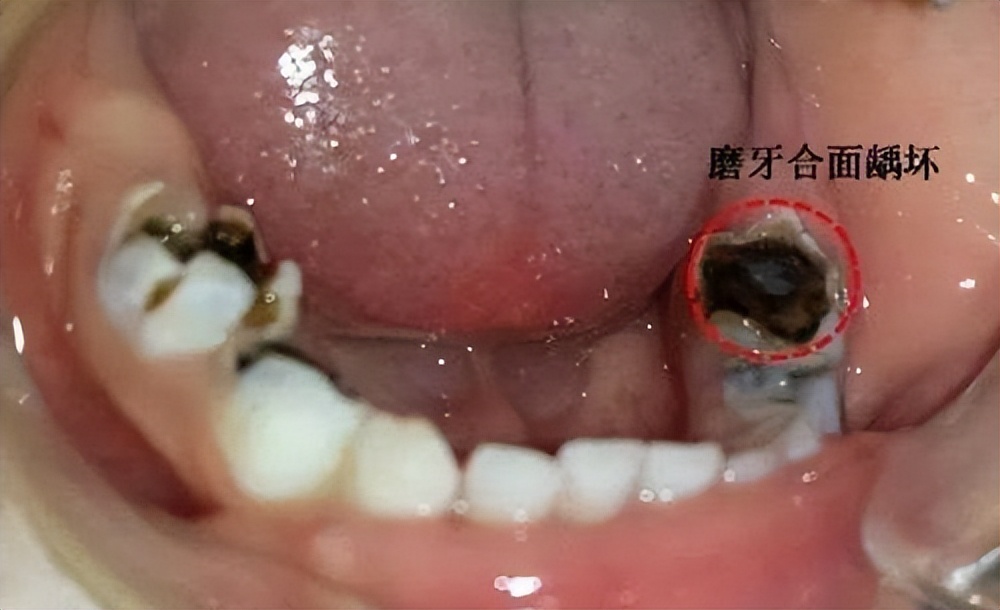

比如这样的:

这样的: